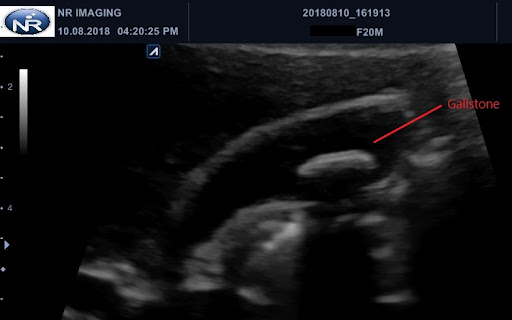

1.3 cm gallstone 267461

Although gallstones are present in about 80% of people with gallbladder cancer, it is uncertain whether gallstones play a role, except when really large stones (greater than 3 Percutaneous transhepatic gallstone extraction (author's transl) Article in German Günther R, Schmidt HD, Braun B Gall stones 13 cm in size were removed in three out of four patients from the common bile duct using a Dormia basket viaGallbladder polyps larger than 15 cm, especially in solitary sessile hypoechogenic polyps, are associated with a risk of malignancy1,3,4,8,34,36 Generally, polyps that are smaller than 1 cm and are asymptomatic are monitored for 6–12 months with control ultrasound scans, in order to detect any rapid growth Gallstones 1 Collection Of Ultrasound Images 1.3 cm gallstone